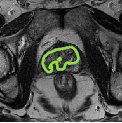

Despite their outstanding accuracy, semi-supervised segmentation methods based on deep neural networks can still yield predictions that are considered anatomically impossible by clinicians, for instance, containing holes or disconnected regions. To solve this problem, we present a Context-aware Virtual Adversarial Training (CaVAT) method for generating anatomically plausible segmentation. Unlike approaches focusing solely on accuracy, our method also considers complex topological constraints like connectivity which cannot be easily modeled in a differentiable loss function. We use adversarial training to generate examples violating the constraints, so the network can learn to avoid making such incorrect predictions on new examples, and employ the Reinforce algorithm to handle non-differentiable segmentation constraints. The proposed method offers a generic and efficient way to add any constraint on top of any segmentation network. Experiments on two clinically-relevant datasets show our method to produce segmentations that are both accurate and anatomically-plausible in terms of region connectivity.